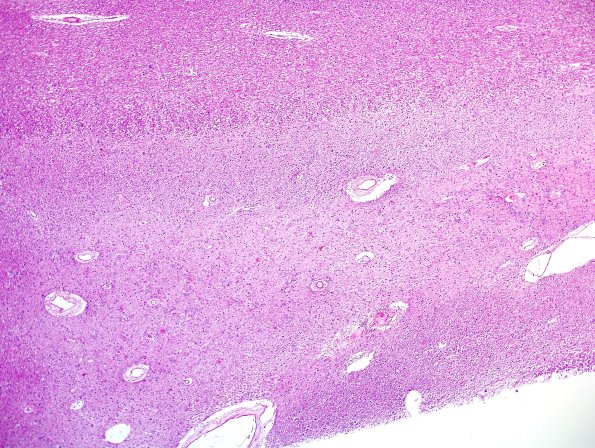

Ependymal Fusion Seam

Multiple magnifications of this occipital fusion seam. (H&E)